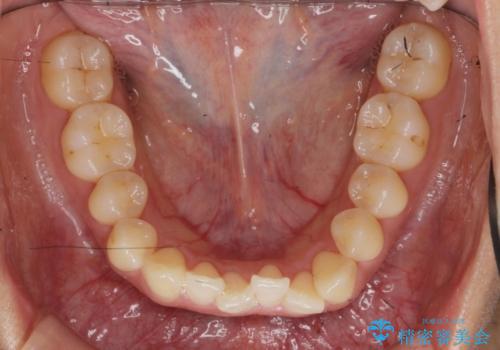

ワイヤー部分矯正治療を併用したマウスピース矯正治療

- 前歯のねじれ、深い噛み合わせ(ディープバイト)の改善を求めて来院されました。

マウスピースでは改善の難しい、歯のねじれ・ディープバイトを部分ワイヤー矯正で改善したのち、マウスピース矯正で全体の歯並びを整えていきます。

部分ワイヤー矯正を行ったことで前歯をしっかりと綺麗な歯並びへと導くことができました。